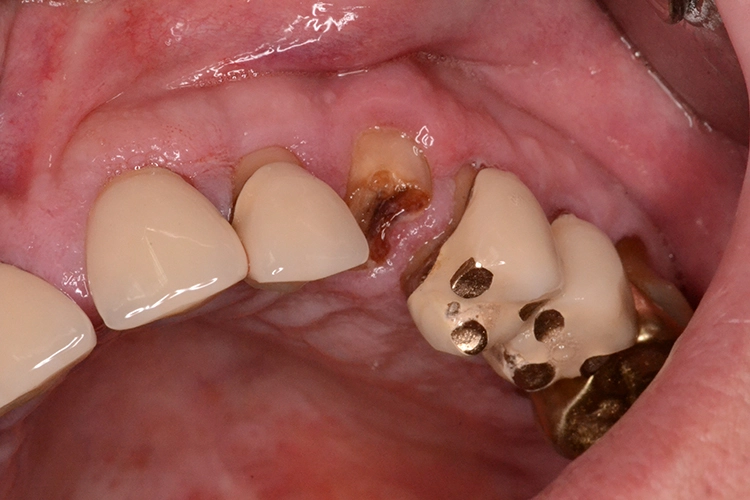

Bei diesem 49-jährigen, allgemeinanamnestisch unauffälligen Patienten liegen diverse ästhetisch störende Zahnstellungsanomalien vor, wobei Zahn 21 bei extremer Elongation frakturierte (Abb. 2a). Nach einer Übergangsversorgung mittels provisorischer Stiftkrone (Abb. 2b) entschied sich der Patient für eine Zahnentfernung bei gleichzeitiger Implantation. Im Ausgangs-DVT (Abb. 2c und d) zeigt sich im Cross-Sectional, wie weit der Processus alveolaris zurückliegt.